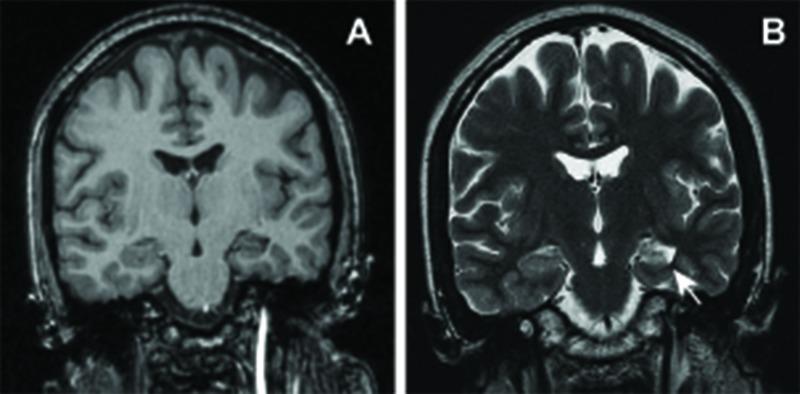

Stereotactic radiosurgery (SRS) is a promising treatment for medically intractable mesial temporal lobe epilepsy. SRS for epilepsy has had an acceptable safety profile with reports of radiation-induced vascular malformations confined to central nervous system pathologies with prominent angiogenesis - namely, primary brain tumors, metastases, and arteriovenous malformations. Theoretical risks for radiation-induced lesions following radiosurgery for epilepsy have yet to be established. Of 13 patients treated in a pilot trial for medial temporal lobe epilepsy, one developed multiple delayed radiation-induced cavernous malformations following radiosurgery. This patient received a prescription dose of 20 Gy delivered to the amygdala, anterior hippocampus, and parahippocampal gyrus. Eight years following treatment, computed tomography imaging demonstrated an evolving hyperdensity in the mesial temporal lobe. Magnetic resonance imaging confirmed multiple T2 hypointense lesions with a mixed-signal intensity core in the left parahippocampal gyrus and anterior temporal lobe. The patient was initially managed conservatively. However, recurrent hemorrhage ultimately caused an acute deterioration in mental status, aphasia, and hemiparesis, necessitating surgical resection. Pathology confirmed radiation-induced cavernous malformations. This represents the first case of a radiation-induced vascular lesion as a long-term sequela of radiosurgery for epilepsy and illustrates the potential for this complication even when low doses are used in patients without angiogenic lesions. Optimal timing and indications for surgical resection of radiation-induced cavernous malformations prior to the development of neurologic symptoms warrant further refinement. Long-term vigilance and clinical monitoring are required.

立体定向放射外科手术(SRS)是治疗药物难治性内侧颞叶癫痫的一种有前景的方法。用于癫痫的SRS具有可接受的安全性,有报告称辐射诱发的血管畸形局限于具有显著血管生成的中枢神经系统病变,即原发性脑肿瘤、转移瘤和动静脉畸形。癫痫放射外科手术后辐射诱发病变的理论风险尚未确定。在一项内侧颞叶癫痫的试点试验中治疗的13例患者中,有1例在放射外科手术后出现了多个延迟性辐射诱发的海绵状畸形。该患者接受了20 Gy的处方剂量,照射杏仁核、前海马体和海马旁回。治疗8年后,计算机断层扫描成像显示内侧颞叶出现逐渐发展的高密度影。磁共振成像证实左侧海马旁回和颞叶前部有多个T2低信号病变,核心为混合信号强度。患者最初采用保守治疗。然而,反复出血最终导致精神状态急性恶化、失语和偏瘫,需要进行手术切除。病理证实为辐射诱发的海绵状畸形。这是首例作为癫痫放射外科手术长期后遗症的辐射诱发血管病变,表明即使在没有血管生成病变的患者中使用低剂量时,这种并发症也有可能发生。在神经症状出现之前,手术切除辐射诱发的海绵状畸形的最佳时机和适应证有待进一步完善。需要长期的警惕和临床监测。